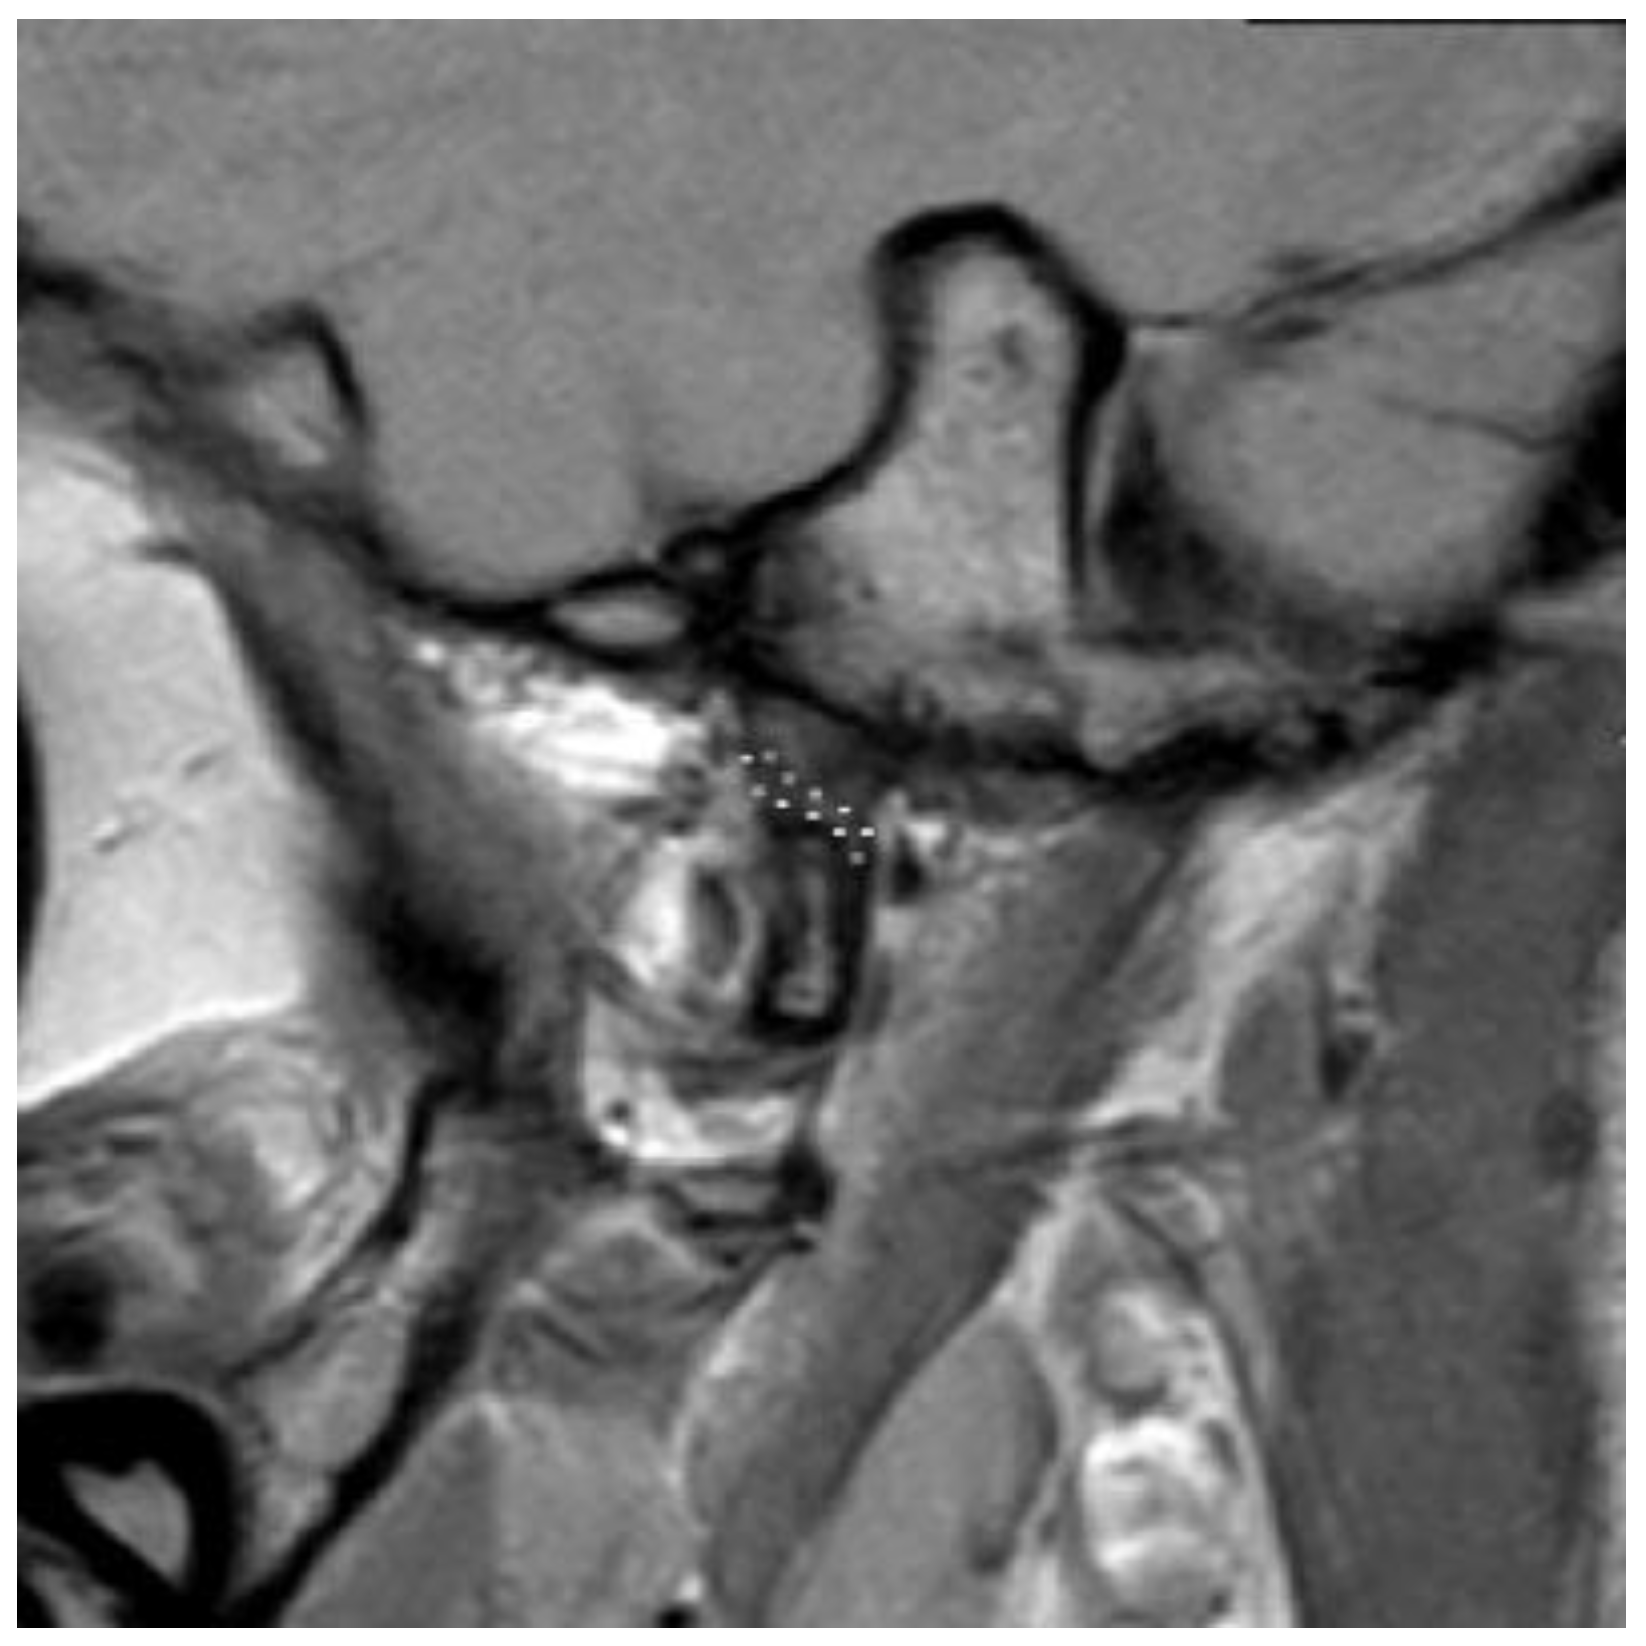

3.2. Definition of Disc Classification